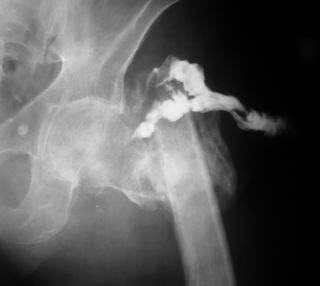

Пациент С., 45 лет, преподаватель одного из ВУЗов г. Москвы, 3 года назад получил чрезвертельный перелом левой бедренной кости, по-поводу чего в одной московских больниц лечился методом скелетного вытяжения. Развилось нагноение в области перелома, после чего имелся свищ по наружной поверхности бедра (рис. 1 - фистулография). Через 1 год воспалительный процесс был купирован. Свищ закрылся самостоятельно.

Имя     : Рис. 1.jpg